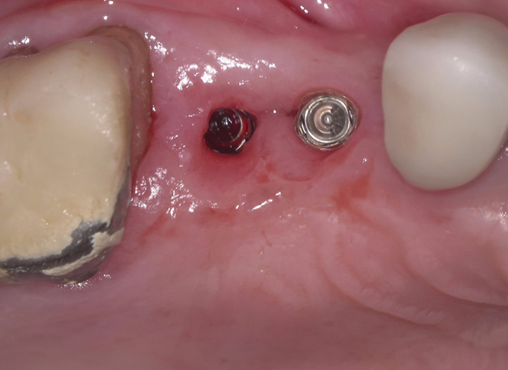

①歯根破折により右上小臼歯が動揺し、歯肉が腫れてしまい、周囲の歯槽骨が吸収していてインプラント埋入

が出来ないと他院で診断され、当院にインプラント治療を希望されました。

①歯槽頂よりサイナス

リフトを行いました。

②血液成分とカルシウム材料により骨造成をしました。

③ガイデッドサージェリーにてインプラント埋入しました。

④計画通りの埋入が出来ました。